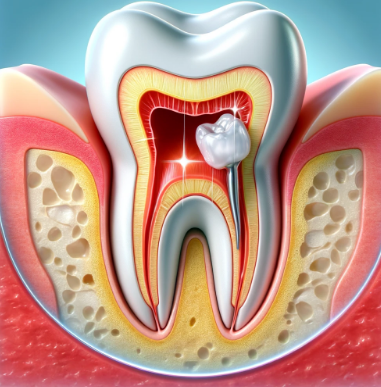

충치 치료의 종류에 대해 알아보기전에 치아의 구성 조직들에 대해 이해하는 것이 필요합니다. 어려울 것 없는데요. 그 구성 조직들이 충치에 감염되는 범위에 따라 충치 종류가 나눠진다고 보시면 되겠습니다. 아래는 치아의 구성 요소입니다.

- 에나멜

- 상아질

- 치수

- 치근

여기서 에나멜은 흔히 말해 겉으로 보이는 가장 바깥쪽의 매우 단단한 하얀색 치아를 말합니다. 그냥 거울을 통해 보았을 때, 육안으로 바로 보이는 것이 에나멜이라고 보시면 되겠습니다. 에나멜이 감염되면 그냥 깍아서 레진 충전을 통해 치료만 하면 됩니다. 가장 경미한 단계이죠.

그 다음 상아질은 에나멜의 내부라고 보시면 되는데요. 미네랄 함량이 적기 때문에 에나멜보다는 부드러운 조직에 속하며 이 때부터 중간 단계라 보시면 됩니다. 상아질에는 관이 있기 때문에 세균이 더욱 빠르게 확산되는데요. 그래서 겉으로 보이는 충치보다 실제 충치는 더욱 큰 범위로 확산되어있는 것이죠.

마지막으로는 치수 입니다. 치아 내부의 연조직으로써 신경과 혈관이 모여있는 곳을 말합니다. 즉 이 때부터는 신경치료의 범위에 해당 하게 됩니다. 이 때 두가지로 나눌 수 있는데요. 신경치료는 다행히 근관치료를 통해 자연치아를 보존할 수 있지만, 감염이 심할 경우 발치와 같은 침습치료가 필요할 수 있습니다.